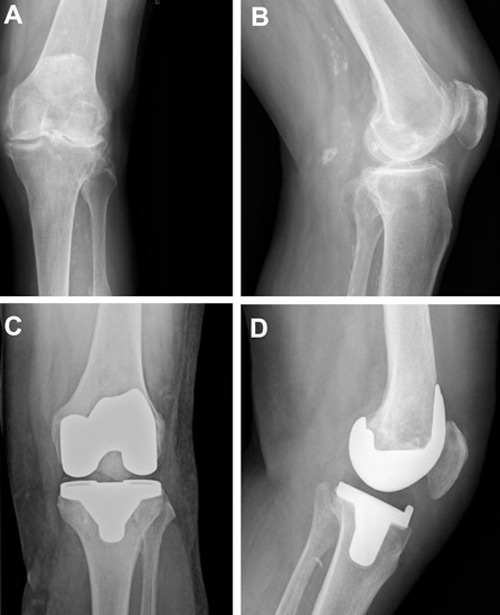

Total knee arthroplasty

The first prosthesis designed to replace all three knee compartments was introduced in 1972 by John Insall. Described as the “total condylar prosthesis”, it achieved very good outcomes and had a huge impact on condylar arthroplasty [35, 36]. Since then, there has been a remarkable increase in the number of TKAs performed annually. In the USA alone, over 700,000 TKAs were performed in 2011, a figure that is expected to increase by more than 600% by 2030 [37]. Figure 4 shows a radiograph of an arthritic knee before and after knee replacement.

Figure 4

A. Anteroposterior X-ray of tricompartmental osteoarthritis. B. Lateral X-ray of tricompartmental osteoarthritis. C. Anteroposterior X-ray following total knee arthroplasty (TKA). D. Lateral X-ray following TKA.